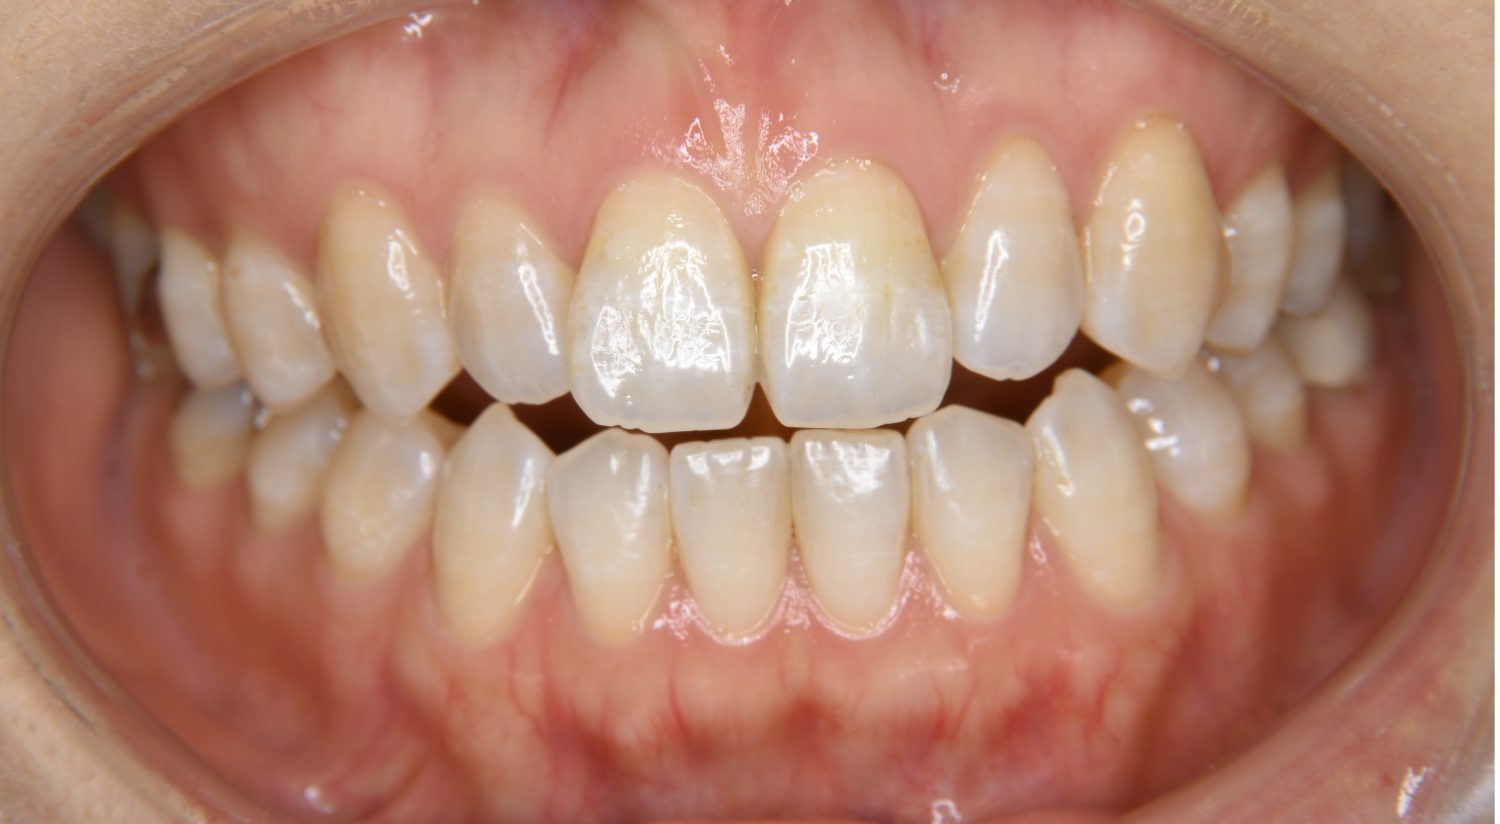

叢生の症例紹介①

Before

主訴

前歯のガタガタが気になる。

治療内容

上顎左側第一小臼歯を抜歯し、アライナー(インビザライン)にて治療を行いました。

治療費

1,150,000 円(税込)

治療期間

23ヶ月

通院回数

13回

想定されたリスク

※歯根吸収、歯肉退縮、歯髄壊死、顎関節症状

※アライナー(インビザライン)は日本の薬機法未承認の矯正装置であり、医薬品副作用被害救済制度の対象外となる場合があります。

左上の側切歯が完全に内側に入り込んでいる状態でした。左上の第一小臼歯のみ抜歯を行い治療を行うことで機能面および審美面を改善しました。